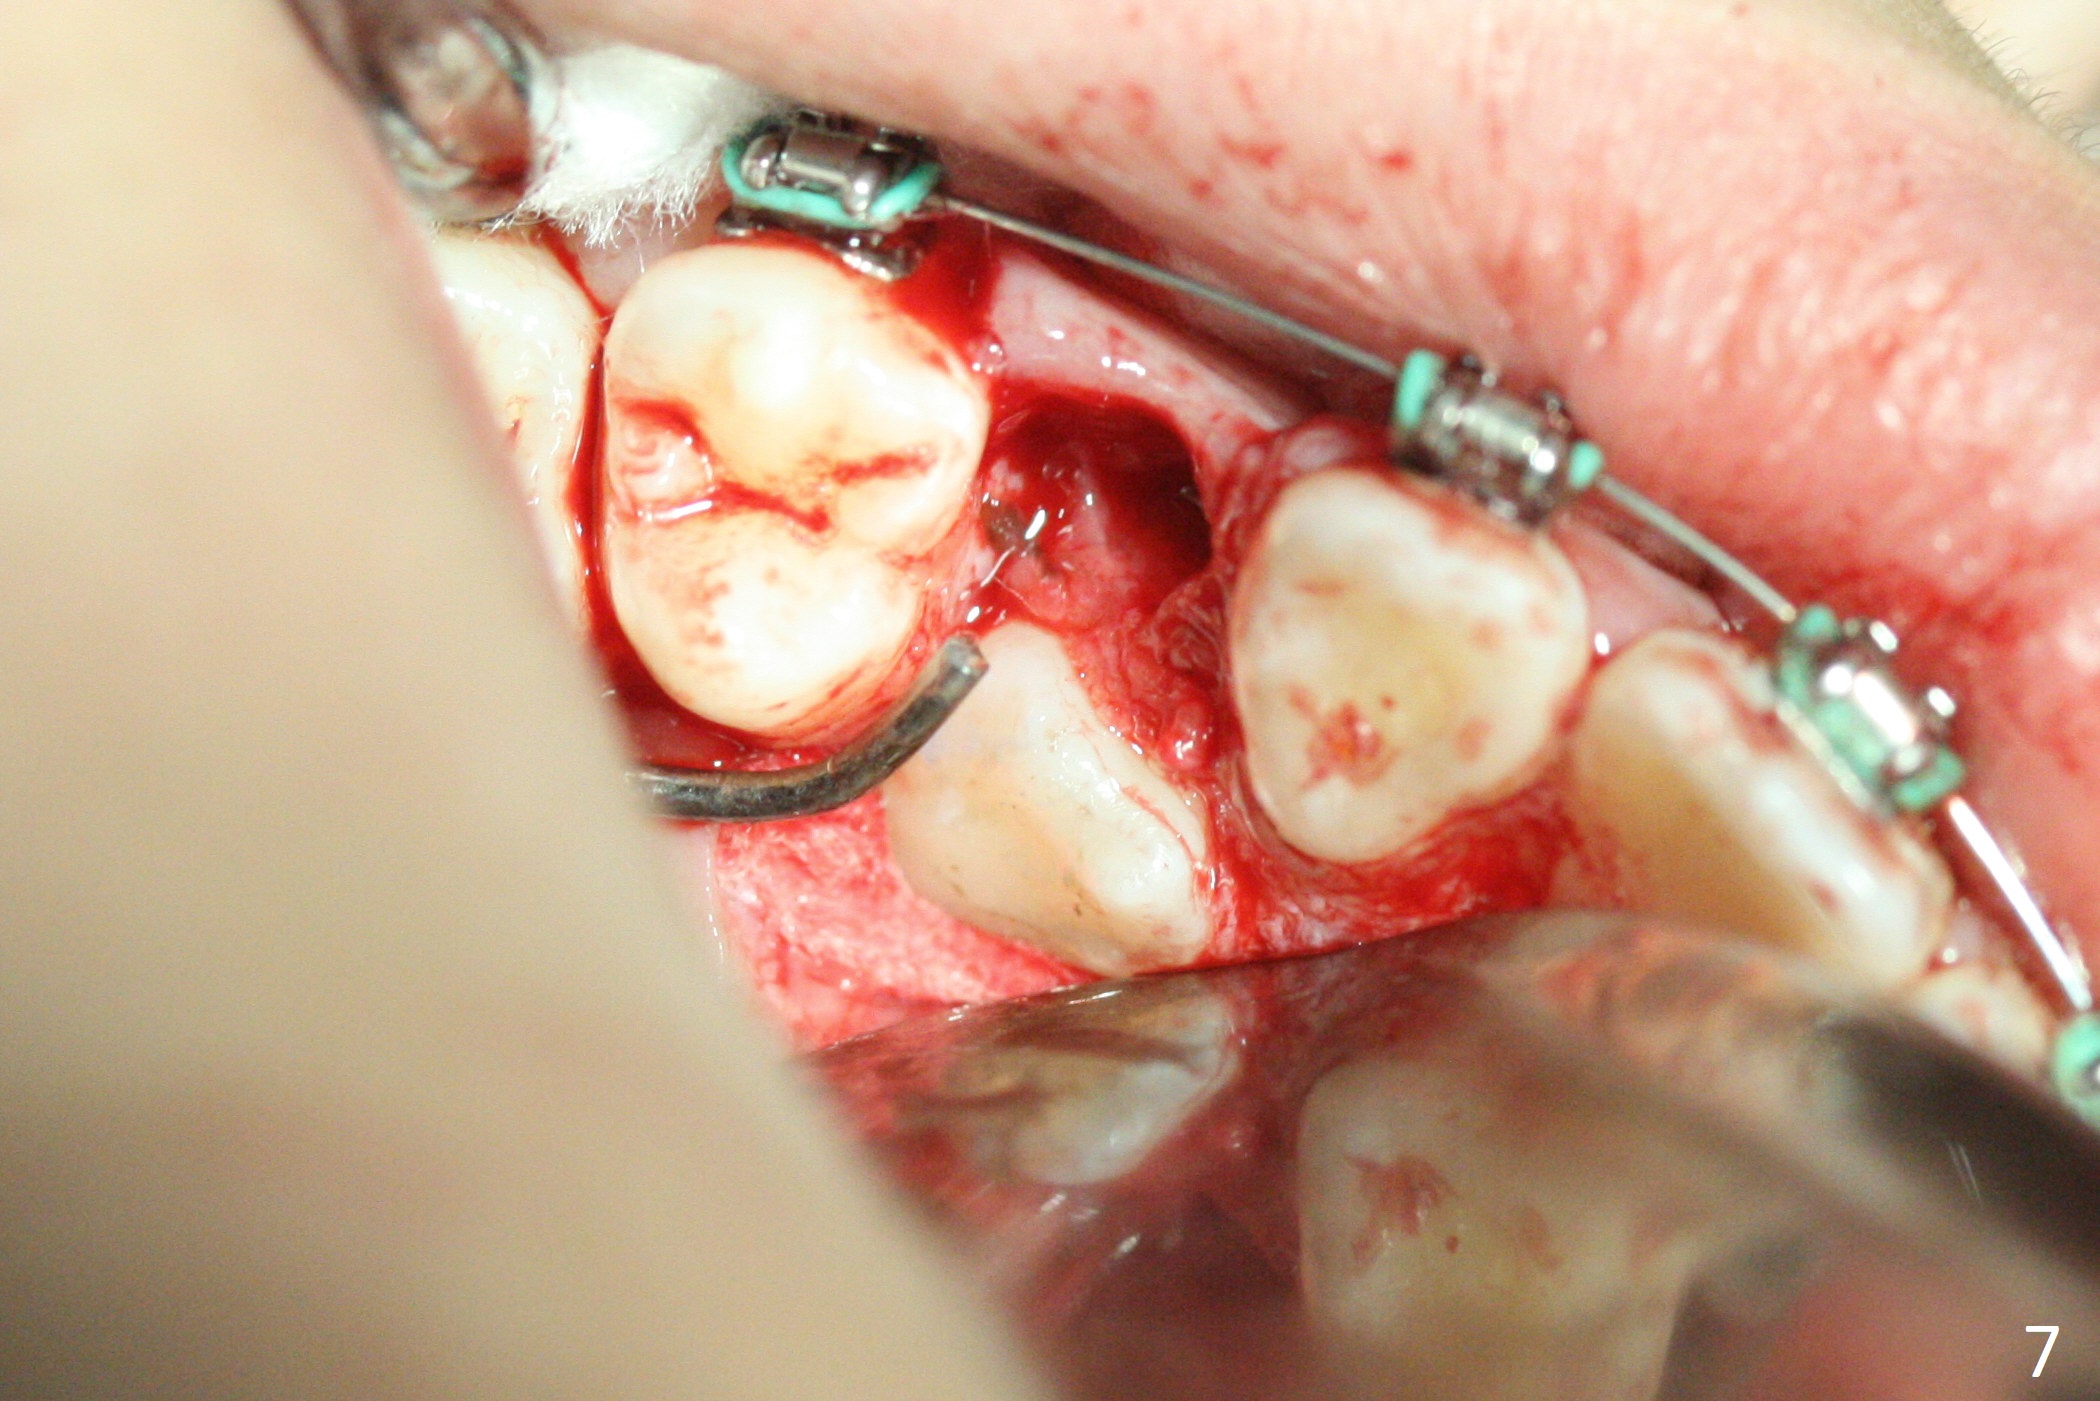

A 13-year-old woman has an impacted canine (Fig.1 (6)) and retained deciduous one (C). After initiation of orthodontics, she returns for surgical access to the impacted canine and placement of device to facilitate eruption (Fig.2,3). Incision is made buccal (Fig.4), but there is no tooth buccal (Fig.5). Extraction of the deciduous canine does not reveal the impacted one (Fig.6), but there is palatal elevation (*). Palatal access shows the impacted tooth (Fig.7) and allows placement of a retraction device (Fig.8). Careful clinical exam and CBCT are necessary diagnostic steps.